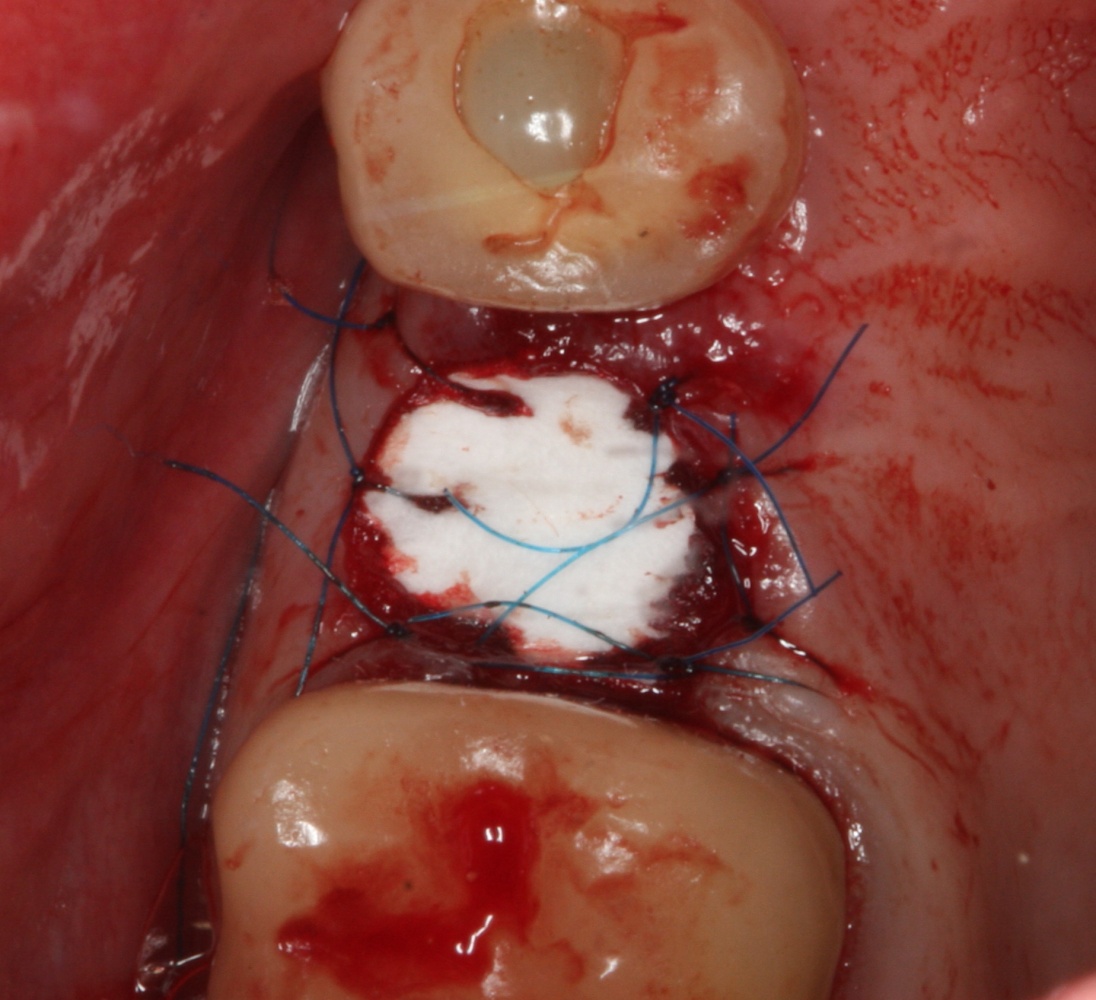

Если на этапе разреза и формирования раны всё сделано правильно, то наложение швов не вызывает особых трудностей. Периостотомия или послабляющие разрезы на периосте не требуются (ни практически никогда не требуются). А сами швы получаются аккуратными и герметичными:

Обрати внимание, что все шовные лигатуры находятся в пределах кератинизированной десны. Это позволяет избежать деформации тканей и лишних рубцов. В наиболее уязвимых местах (около зубов) шовные лигатуры лучше продублировать.